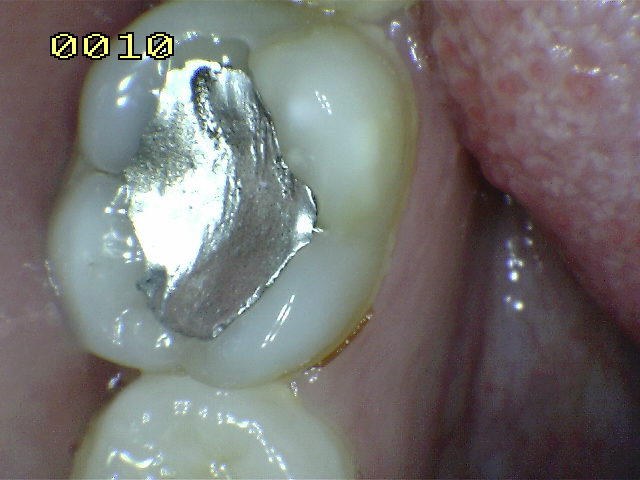

| Amalgama de 5 años , observe el desbordamiento por el

típico flow de la amalgama en el borde cavo superficial. |